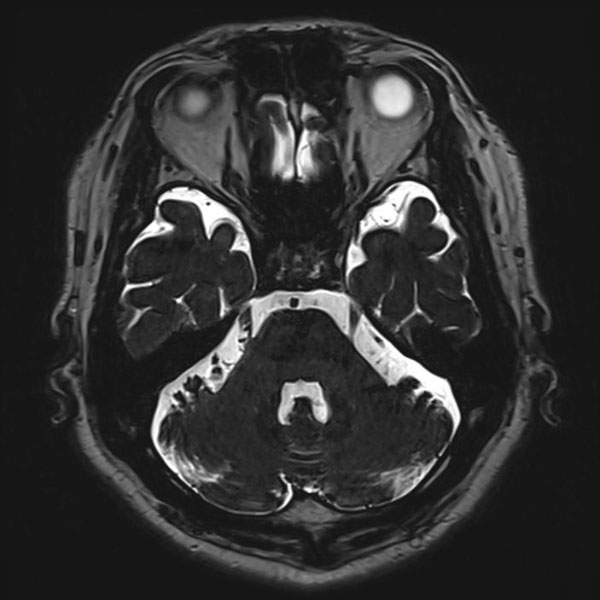

580

兵庫県の病院

'26年2月

70代

右三叉神経痛

減圧後